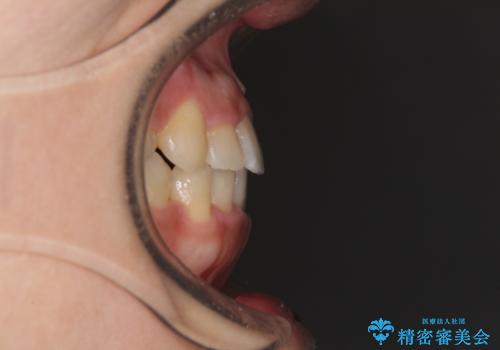

前歯の反対咬合 非抜歯のワイヤー矯正

- 前歯のでこぼこを気にして来院された患者様です。

マウスピース矯正の自己管理が面倒くさいことと、治療を早く終わらせたいとのことで、目立ちにくいワイヤー矯正にて歯列を整えることとしました。

1年半はかかると思っていた治療期間ですが、反対咬合となっている前歯が思いの外早く動き、僅か9ヶ月で終了させることができました。

前歯を気にせず笑えるようになり、患者様には大変満足していただきました。